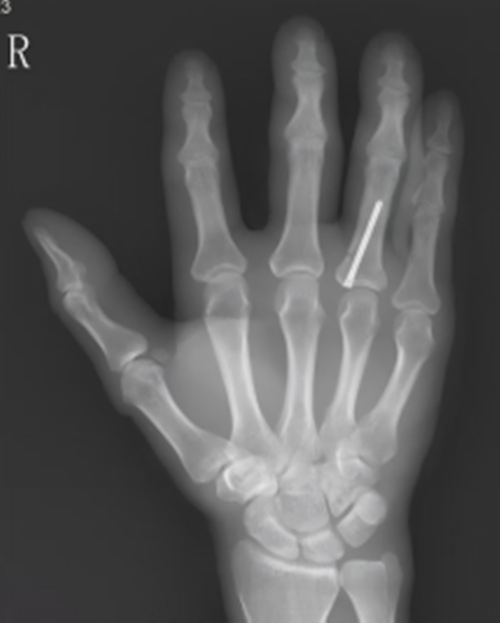

术后影像

针对上述难题,宁德市闽东医院创伤骨科何晓宇主任医师团队经过反复临床实践与技术攻关,成功引入并推广了微创置钉技术。该技术依托精准的术前影像学评估,仅需一个不到5毫米的微小切口,即可完成骨折的稳定固定。与传统方法相比,微创置钉最大程度减少了对软组织和肌腱的损伤,术后手指肿胀轻、疼痛感小,为患者早期开展功能锻炼创造了有利条件。